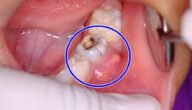

ما هو خراج الاسنان وعلاجه